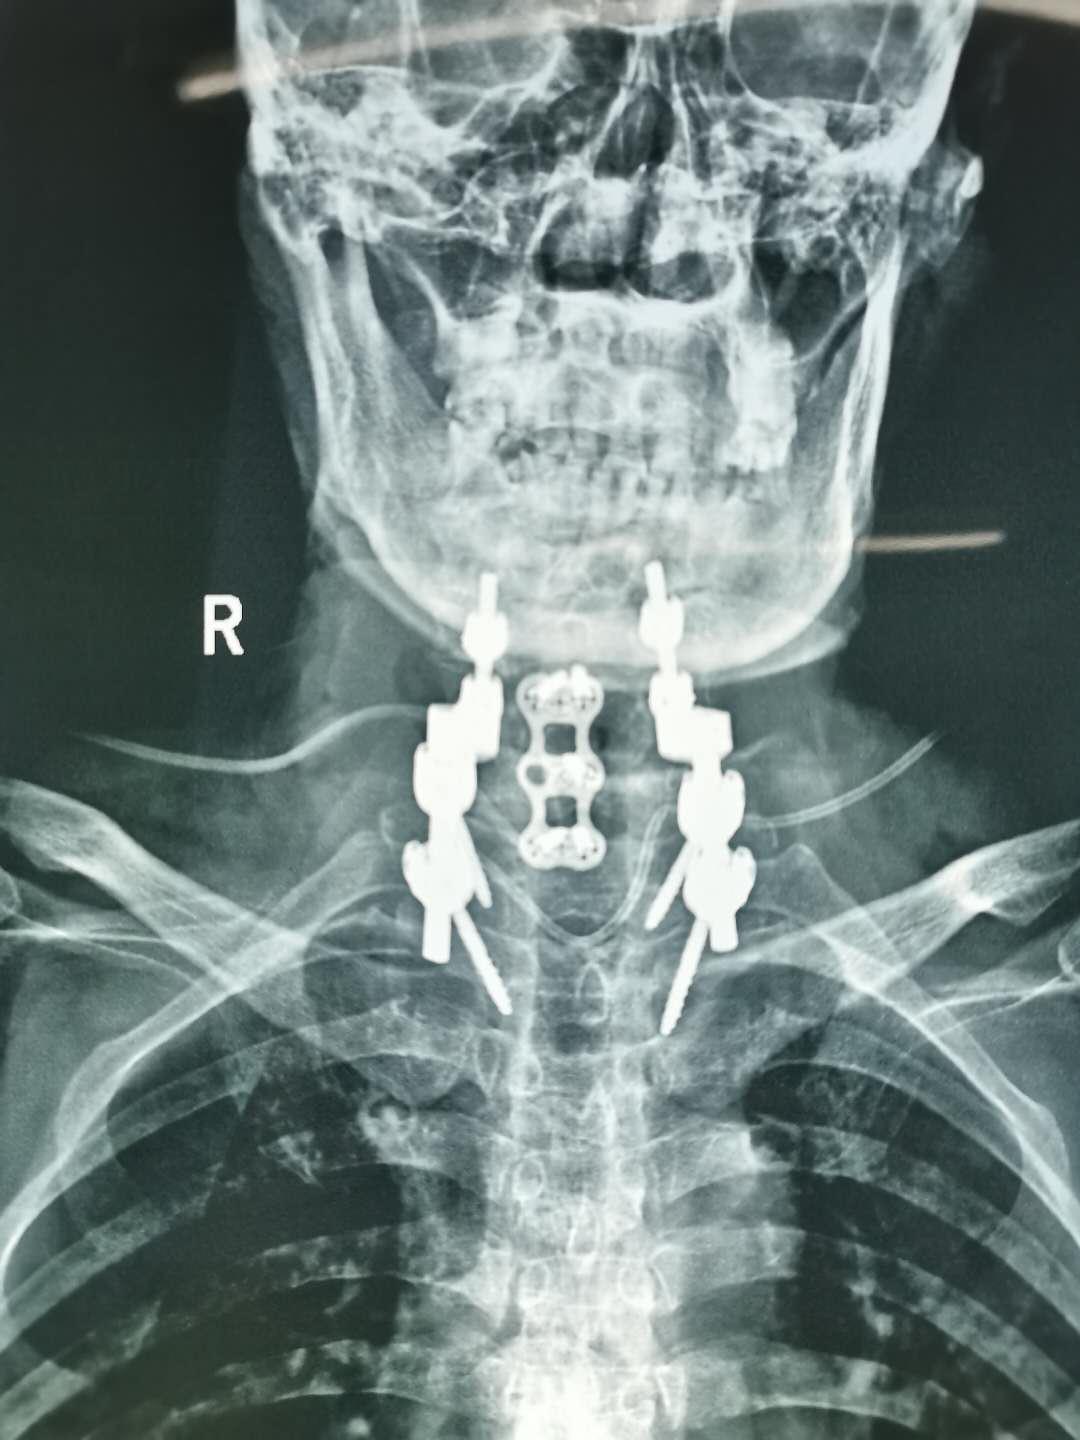

王先生今年64岁,入院时乳头以下全身麻木、不能走路、二便障碍,经核磁及CT检查发现“颈6椎体占位性病变”,且从发病至不能走路只经历约1个月时间,如不能得到及时治疗,患者出现高位截瘫的风险非常高。经市二院骨科医院骨八科主任田晓东(院长助理)及其团队的精心治疗,为患者进行颈胸段前后路联合手术、病灶清除内固定手术,术后一周,王先生感觉麻木消失,能自行下床活动,目前王先生恢复良好。

术后影像

此种颈胸段前后路联合手术,难度较大,辽西地区鲜有开展,锦州二院独立完成此手术,无疑让骨病患者重塑健康信心,给骨病患者带来健康福音。